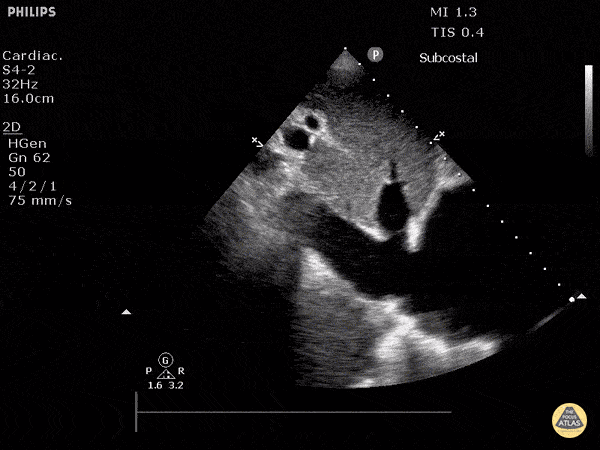

54M smoker + Exertional CP, ?ACS

D Sign + McConnell's Sign

Evidence: https://www.ncbi.nlm.nih.gov/pubmed/26973178

Example: http://www.thepocusatlas.com/right-ventricle

Tutorial: https://westernsono.ca/screencasts/echo/mcconnells-sign-acute-pulmonary-embolism/